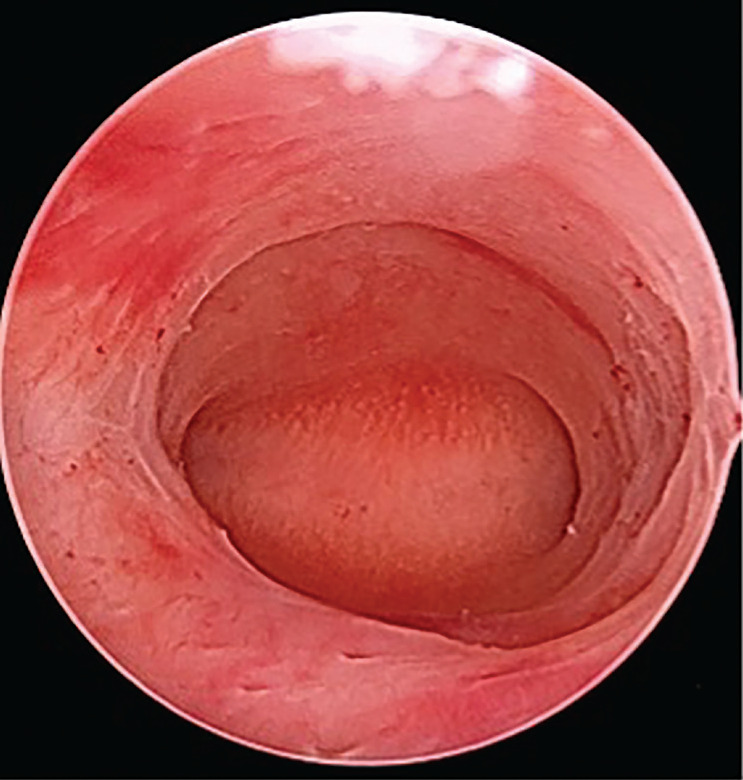

Results: The review revealed distinct characteristics of infantile uterus and uterine hypoplasia. The infantile uterus has a body/cervix ratio of 1:1 or 1:2, resembling that of a prepubescent girl, while uterine hypoplasia maintains a normal body/cervix ratio of 2:1 but is smaller in size. Diagnostic criteria include a total uterine length of less than 6 cm and specific ultrasound features such as reduced intercornual distance. Therapeutic options include hormonal therapy, particularly oestrogen administration, and surgical interventions aimed at expanding the uterine cavity. Hormonal treatments showed variable effectiveness, primarily beneficial in cases of oestrogen deficiency, while surgical approaches demonstrated some success in enhancing fertility outcomes in women with a hypoplastic uterus.